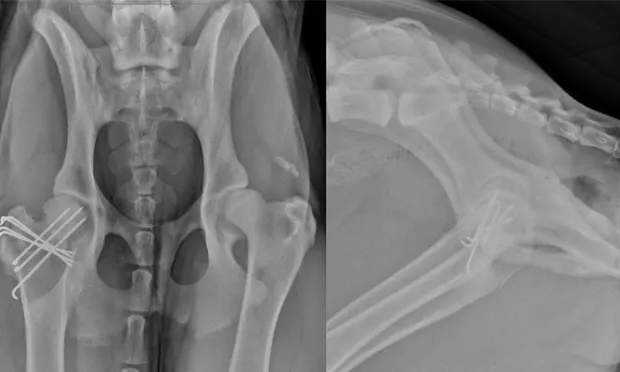

VD and lateral x-rays of dog’s pelvis showing orthopedic wires within the proximal aspect of the right femur.